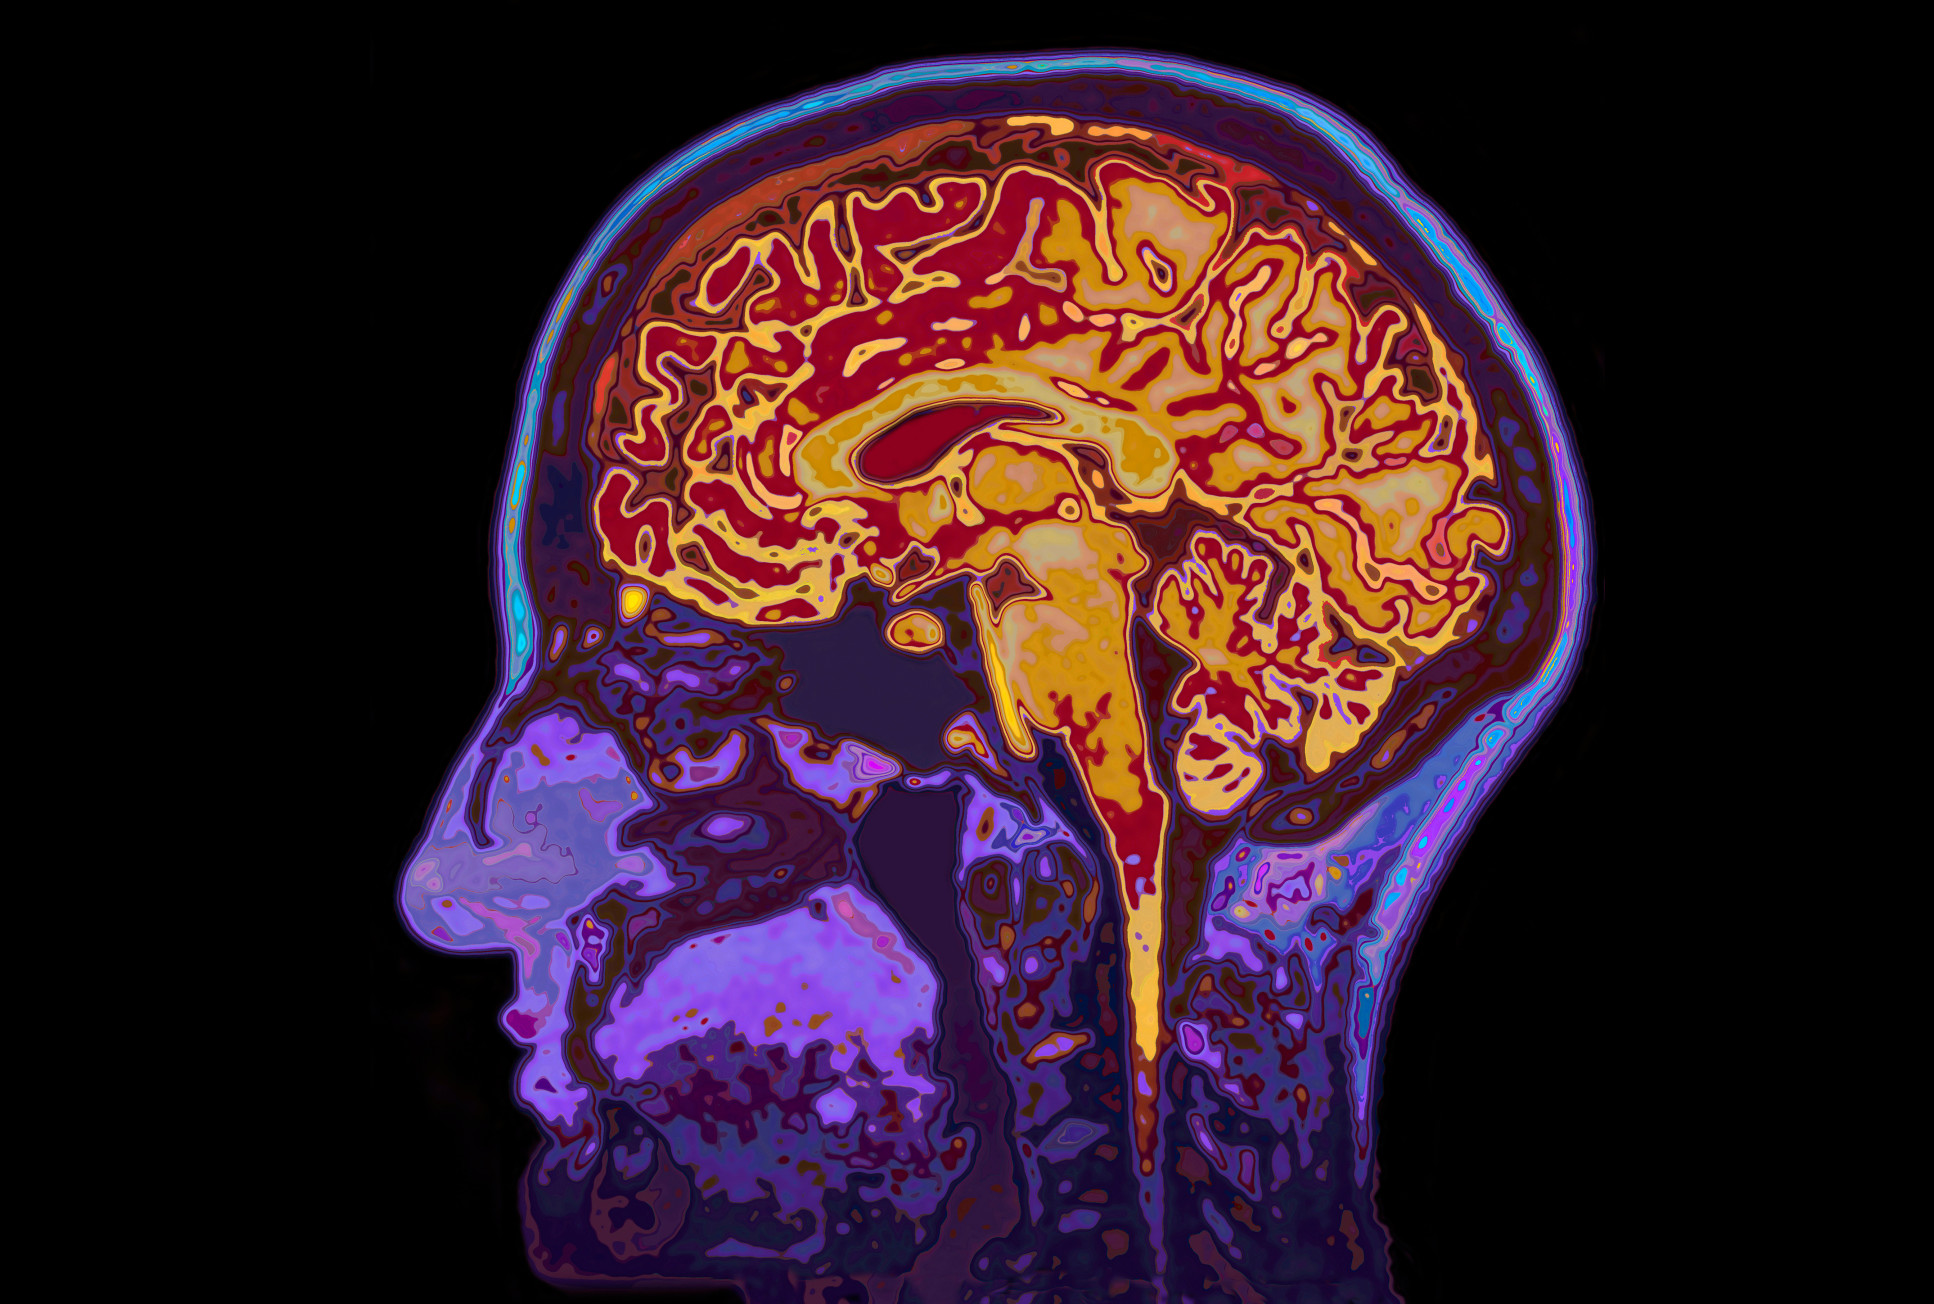

10 brainy and mental health stories from 2021